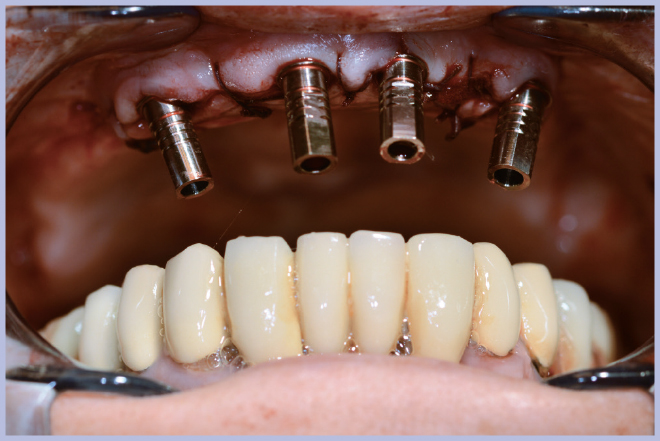

Dopo l’estrazione dei 3 elementi residui (Fig. 2), sono stati posizionati 4 impianti Max Stability Ø3,75 mm (2 di lunghezza 10 mm e 2 di lunghezza 12 mm).

Dopo il posizionamento implantare si sono utilizzati 4 monconi per protesi avvitata angolati a 25°. Dato che non si è utilizzato alcun modello in gesso ma si è lavorato direttamente in bocca, la procedura ottimale in questi casi è quella di rimuovere dai monconi gli esagoni Exacone® 360°.

Per la scelta dei monconi, in termini di altezza del tratto transmucoso e angolazione, si è utilizzato il kit di monconi di prova Standard-Large. Quindi si sono prelevati i monconi definitivi dal kit Leone All-on-Four/All-on-Six fornitoci in conto visione: questo servizio offerto dall’azienda ci consente di fare a meno di un magazzino dei componenti protesici, permettendone l’acquisto dopo aver già selezionato le misure di interesse.

- Fig. 3 – Posizionamento dei monconi per protesi avvitata